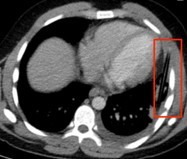

空调与精神病,两个看起来风马牛不相及的东西,被热浪袭击联系在了一起。尽管精神病,比如精神分裂症患者本身可能合并体温调节障碍,但显而易见,精神病人在热浪来袭时没有打开空调,是其致死的重要原因。抛开有关理性缺失的探讨,精神病人,尤其是精神分裂症患者对感觉的迟钝可能是造成惨剧的根本。有一个极端的例子可以印证:美国一名24岁的精神分裂症患者因为企图服药自杀被送进了医院,入院以后另一个病人向医生报告说亲眼看到他把一个东西插到了胸腔里,查体发现病人胸部有一个针尖大小的伤口,X线和CT也没有发现异常,也就没有在意,只给了常规的抗感染治疗。但是之后三个周,病人的病情逐渐加重,出现了明显的感染迹象。再回顾影像学资料,才发现胸部有一个异物,手术最终证实是一支铅笔。整个过程中,病人几乎没有多少胸部疼痛的症状。有精神疾病的人,症状和病情不符的情况比常人更加常见和离谱。